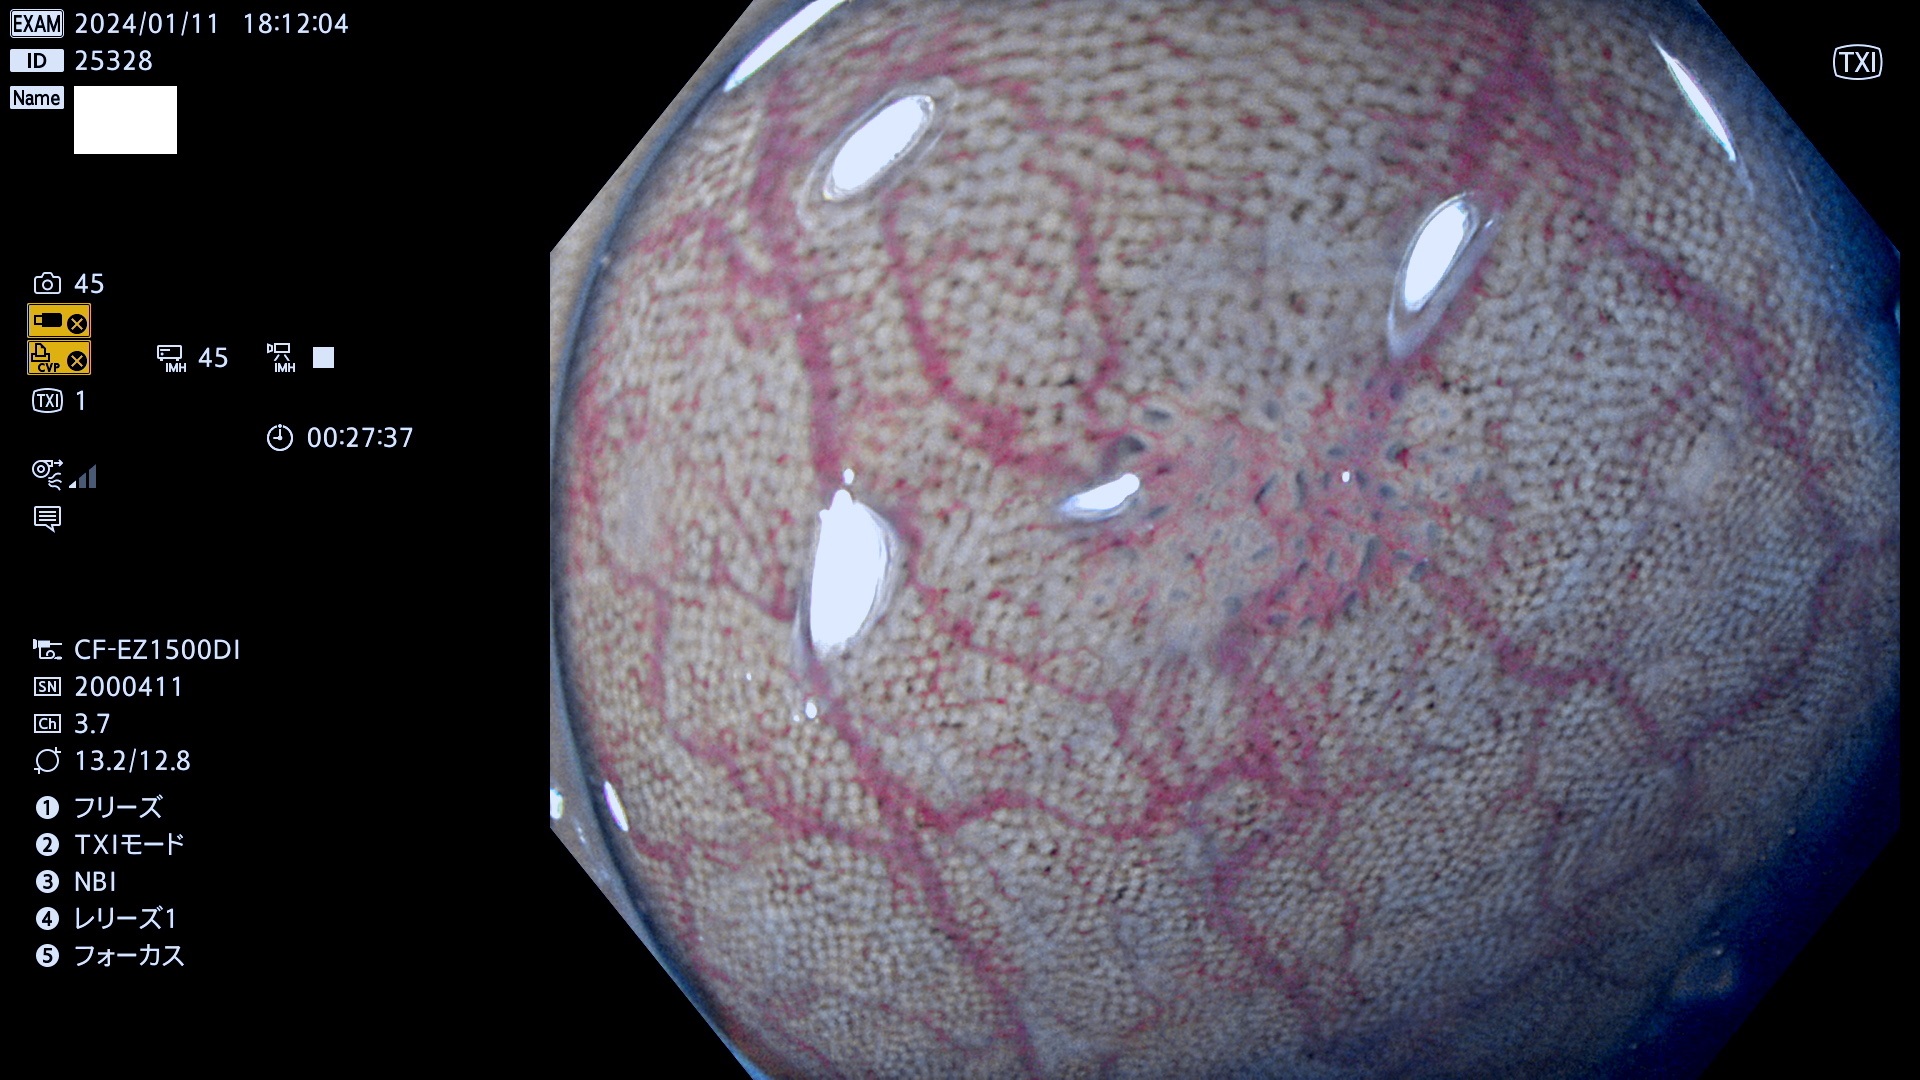

表面型腺腫(Flat Adenoma)の中で、完全に平坦な物をUb、陥凹している物をUcと呼びます。平坦隆起型(Ua)よりも、発見が難しく危険な病変です。

毎週の検査(木・金・土・日)に発見されたUb、Uc型・腺腫を、その週の日曜の夜にUPし1週間、提示します。

抽出の対象期間 2024年1月11日(木))〜1月14(日)の4日間(40件の検査)9件